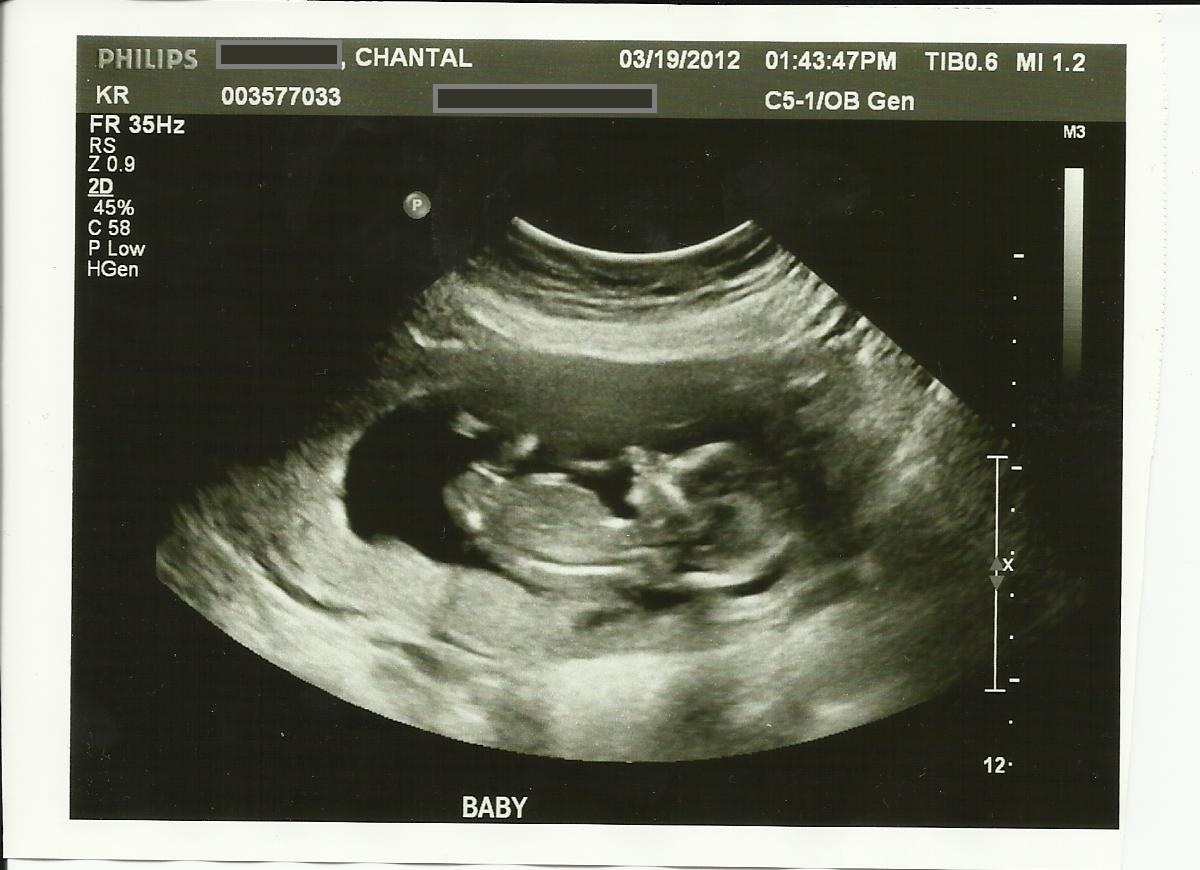

Skull guess please!

This is my ultrasound from 13 weeks 5 days. The tech did a quick crotch shot, but wouldn't look too hard. I am studing to be a Radiologist and I know that I for sure didn't see a nub.

Any guesses on the skull?? To me, the skull and chin look more female like, especially compared to my son's ultrasound photos!

Attachment 1763Attachment 1764Attachment 1765

I think the nub looks like a girl.

Do you mean you didnt see a willy in the potty shot? I see the nub in your first pic, it does look girly.